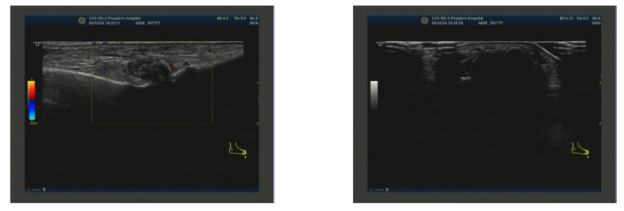

图3. 第一跖趾关节浅表超声2024-04-18 左侧腕关节浅表超声:左侧腕关节滑膜增厚伴痛风石形成;左侧腕关节少量积液(图4)。

图4. 左侧腕关节浅表超声2025-01-21 右膝关节浅表超声:右侧膝关节积液;右侧膝关节滑膜炎伴痛风石形成,可见骨侵蚀;右侧股四头肌腱内强回声(痛风石?);右小腿软组织水肿(图5)。